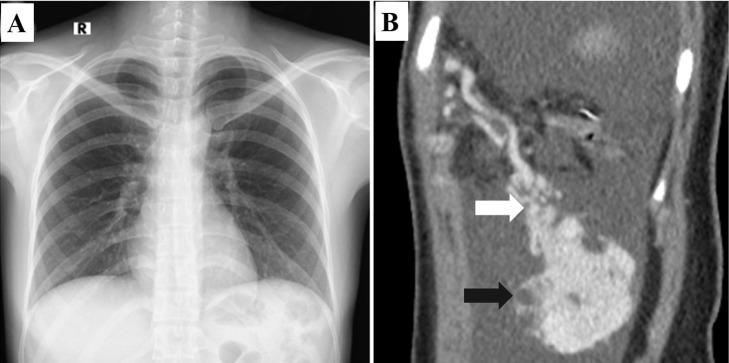

Intra-abdominal solitary fibrous tumor (SFT), also known as hemangiopericytoma, is rare, especially for those with a mesenteric location, and only a few cases have been reported. Distinguishing a hemangiopericytoma from other intra-abdominal benign or malignant tumors can be difficult, as they have similar presentations on both computed tomography and magnetic resonance imaging. In the present study, the records for a 31-year-old Vietnamese woman who underwent abdominal surgery for greater omental tumor resection and received histopathological results revealing SFT are retrospectively reviewed. The case is discussed and similar reported cases are reviewed. Due to the aggressive behavior and high rate of postoperative recurrence associated with SFT, a thorough understanding of the radiologic and histopathological features of the disease is necessary to achieve an appropriate diagnosis and treatment.